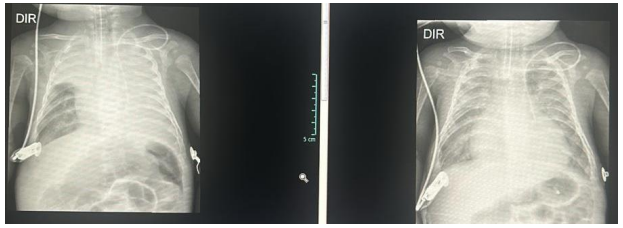

Paciente de 3 meses, pesando 5Kg, nascido termo, parto vaginal e com calendário vacinal atualizado está internado

com hipótese diagnóstica de bronquiolite. No segundo dia de internamento, evoluiu com piora do padrão

respiratório, com importante tiragem subcostal, tiragem intercostal, retração de fúrcula e batimentos de asa nasal.

A ausculta pulmonar, que era simétrica e com estertores e sibilos difusos, evoluiu com assimetria e significativa

redução à esquerda. Após 2 horas de ventilação não invasiva, paciente seguia com quadro de desconforto

respiratório e saturação periférica de oxigênio máxima de 87% com FiO2 50%. Você optou por intubar paciente.

Seguem as imagens referentes ao momento imediatamente posterior à intubação e 6 horas após o início da ventilação mecânica.

Diante do caso, qual complicação o paciente apresentou, sua conduta e materiais utilizados?